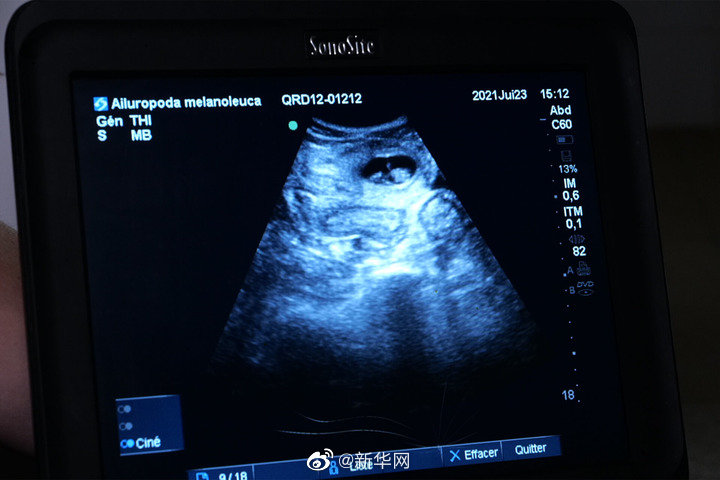

位于法国中部的圣艾尼昂市博瓦勒野生动物园23日宣布,中国旅法大熊猫“欢欢”将诞下双胞胎。博瓦勒野生动物园当天发表新闻公报说,继20日发现“欢欢”腹中首个胚胎后,动物园兽医23日在为“欢欢”做超声波检查时,在其子宫另一侧发现第二个胚胎。新闻公报说,双胎妊娠现象在野生大熊猫中并不罕见,发生率约为50%。